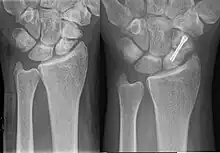

Dans le cas d'une fracture, trois techniques de soins sont applicables :

- immobilisation prolongée du poignet et de l'avant-bras (plâtre ou résine) pendant 90 jours,

- fixation en chirurgie ambulatoire par technique percutanée,

- vissage en chirurgie classique à ciel ouvert.

Les techniques applicables dépendent du type de fracture et de sa localisation sur l'os. Pour les fractures non déplacées, principalement celles du corps du scaphoïde, la technique percutanée tend à se développer. Elle s'opère sous anesthésie locale, sans hospitalisation du patient, et dure environ 20 à 30 minutes. Ses résultats sont excellents, et la durée d'immobilisation consécutive est réduite à environ deux semaines (contre 8 à 12 semaines sans intervention). Toutefois, un traitement par immobilisation, dans les formes médiales, avec contrôle radiologique et intervention chirurgicale s'il n' y a pas de signe de consolidation, expose à moins de complications qu'une chirurgie immédiate, avec un résultat fonctionnel aussi bon[10].